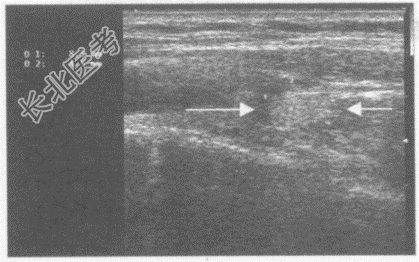

- 单项选择题女,47岁, 自诉右乳癌术后2年,感觉右颈部不适。超声综合描述: 右侧颈总动脉外侧可见0.8cm×0.4cm椭圆形增强回声区(箭头所示),内回声不均, 与周围组织粘连,用探头推压, 位置无变化。超声提示:

A、右侧甲状腺腺瘤

B、右侧颈总动脉旁肿大淋巴结(右颈部淋巴结转移瘤)

C、正常右侧甲状旁腺声像图

D、甲状腺右叶结节

E、右颈部淋巴结结核